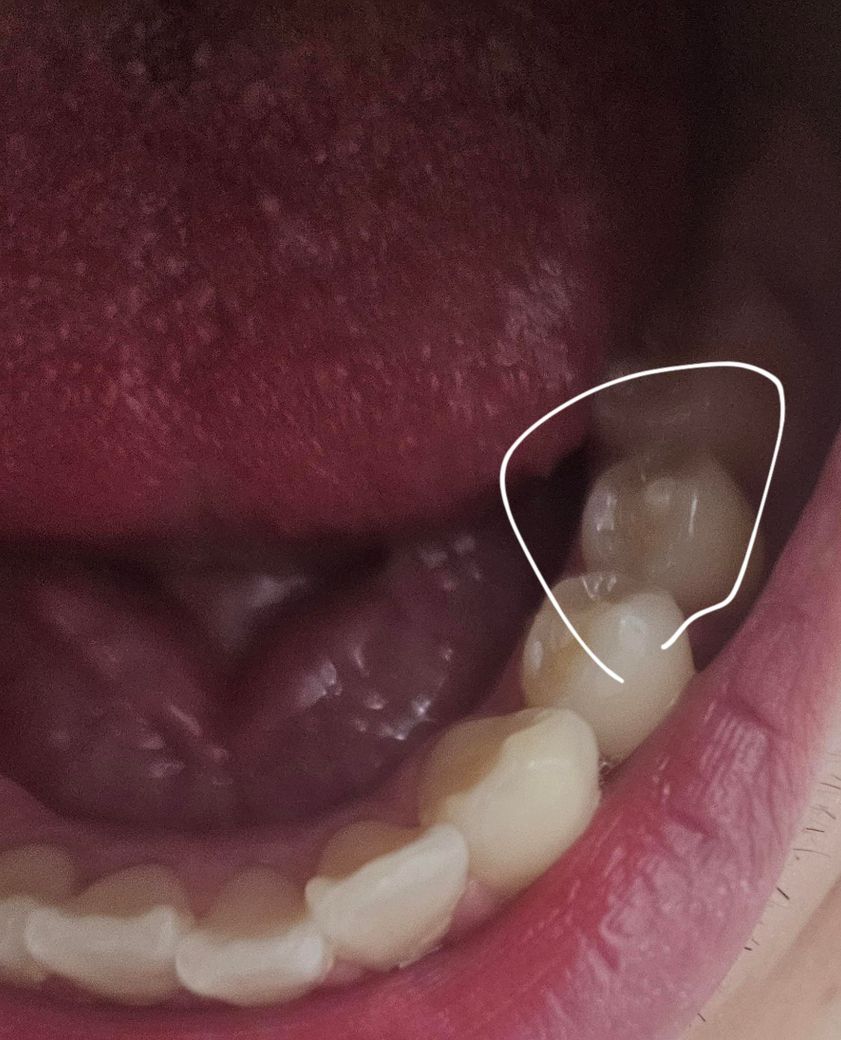

치외치로 보이는 이빨이 있는데 통증은 없는데 놔둬도 댈까여?

치외치로 보이는 이빨이 발견되었는데여 몰랐는데 부숴진지는 오래됬고 그동안 문제는 없었는데 오늘 처음 치외치를 알게되었습니다. 어찌 해야하나여?

치매치가 있어도 특별히 통증이 없고 불편감이 없다면 특별한 치료를 할 필요는 없습니다. 치위치가 있는 부분은 신경이 따라 올라와 있는 경우가 많기 때문에 너무 과도한 힘이 가해져서 파절되지 않도록 하는 것이 중요합니다.

치외치는 문제가 없다면 그냥 사용하셔도 크게 상관없습니다. 혹시라도 치외치가 깨진경우 치아가 시릴수 잇으니 깨지는것만 조심하시면됩니다.

특별히 해줄 수 있는게 따로 없습니다 파절이 일어나지 않도록 특히 주의해서 사용하셔야 합니다